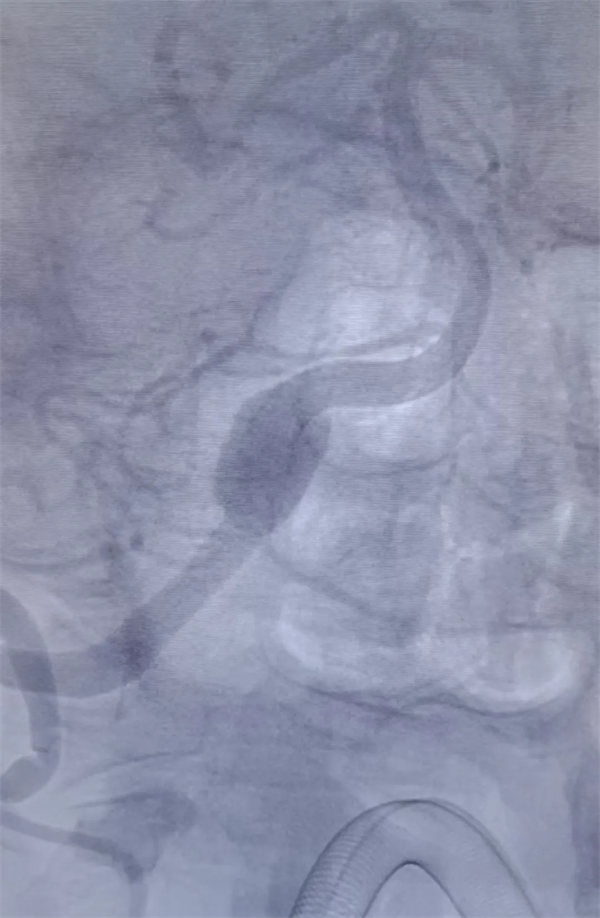

在完善术前准备后,手术团队精准操作,顺利为患者植入血流导向装置。术后即刻造影显示,动脉瘤体内血流速度明显减慢,手术取得预期效果。术后,医护团队为患者制定个性化康复与用药方案,叮嘱患者规律服药,预计3-6个月后动脉瘤将完全闭塞,脑血管实现完美重建。目前患者恢复良好,头晕症状显著缓解,已顺利进入术后康复阶段。

血流导向:其细密的网孔能显著减少进入动脉瘤的血流,导致瘤内血流停滞、形成血栓,最终使动脉瘤闭塞。

血管重建:支架的网孔为血管内皮细胞生长提供了“脚手架”,引导其攀爬覆盖瘤颈,最终在血管内壁形成一层新的生物膜,将动脉瘤彻底隔绝在血液循环之外,实现解剖愈合。